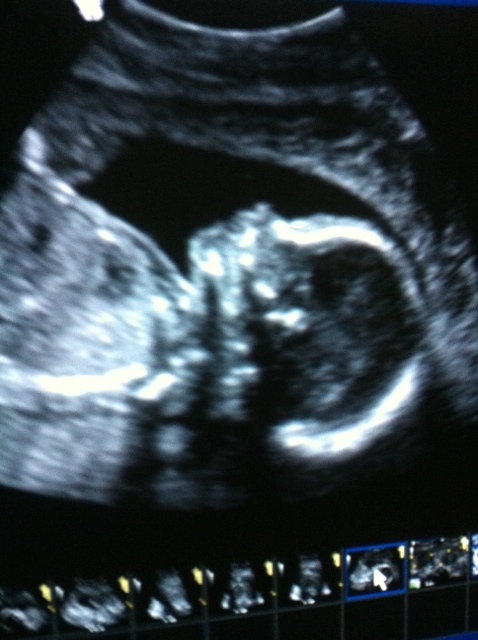

Yay!! I had the a/s yesterday and the tech said everything looked good; although she spent a lot of time taking pics of the heart so I'm half worried...

Baby GIRL was 9oz and I'm over the moon excited that we aren't having the same umbilical cord issue as we did with DS. I won't be relieved until our followup appt. with the doc to go over the results but for now I'm one happy mama